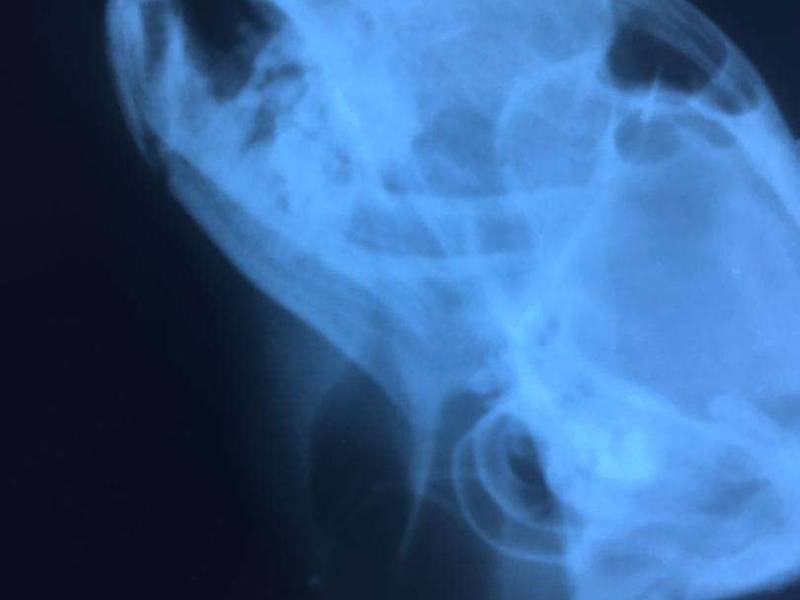

دامپزشکان با کمک رادیولوژی حیوانات میتوانند دید بهتری نسبت به مشکلات حیوانات داشته باشند و با کمک این دید درمان های تأثیرگذارتری را برای حیوانات خانگی در نظر میگیرند. از جمله دغدغههای مهمی که صاحبان حیوانات خانگی دچار آن میشوند،یکی از نکاتی که در زمان انجام رادیولوژی و mri حیوانات خانگی به ویژه سگ ها و پرندگان باید به آن دقت کرد این است که رادیولوژی به تخصص نیاز دارد و ممکن است هر دامپزشکی نتواند این کار را انجام میدهد. زیرا در امور تشخیصی و درمانی برای حیوانات نیز مانند افراد به تخصص کافی نیاز میباشد.